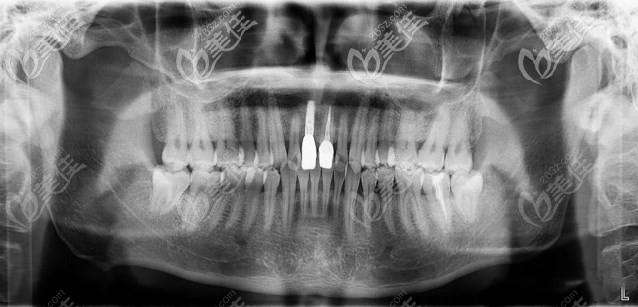

经口腔数据分析,间隙充足,邻牙健康,适合种植。

CT:显示大门牙牙位牙槽骨唇腭向距离月7.78mm,牙槽嵴顶到鼻底约28mm,适合种植牙。